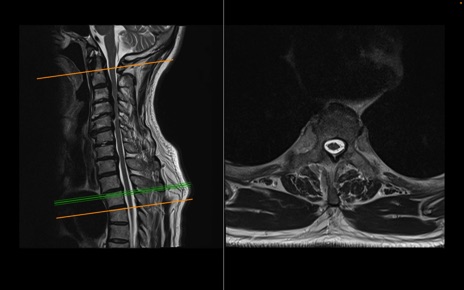

頚椎MRI

T2WI(横断像)

T2WI(矢状断像)